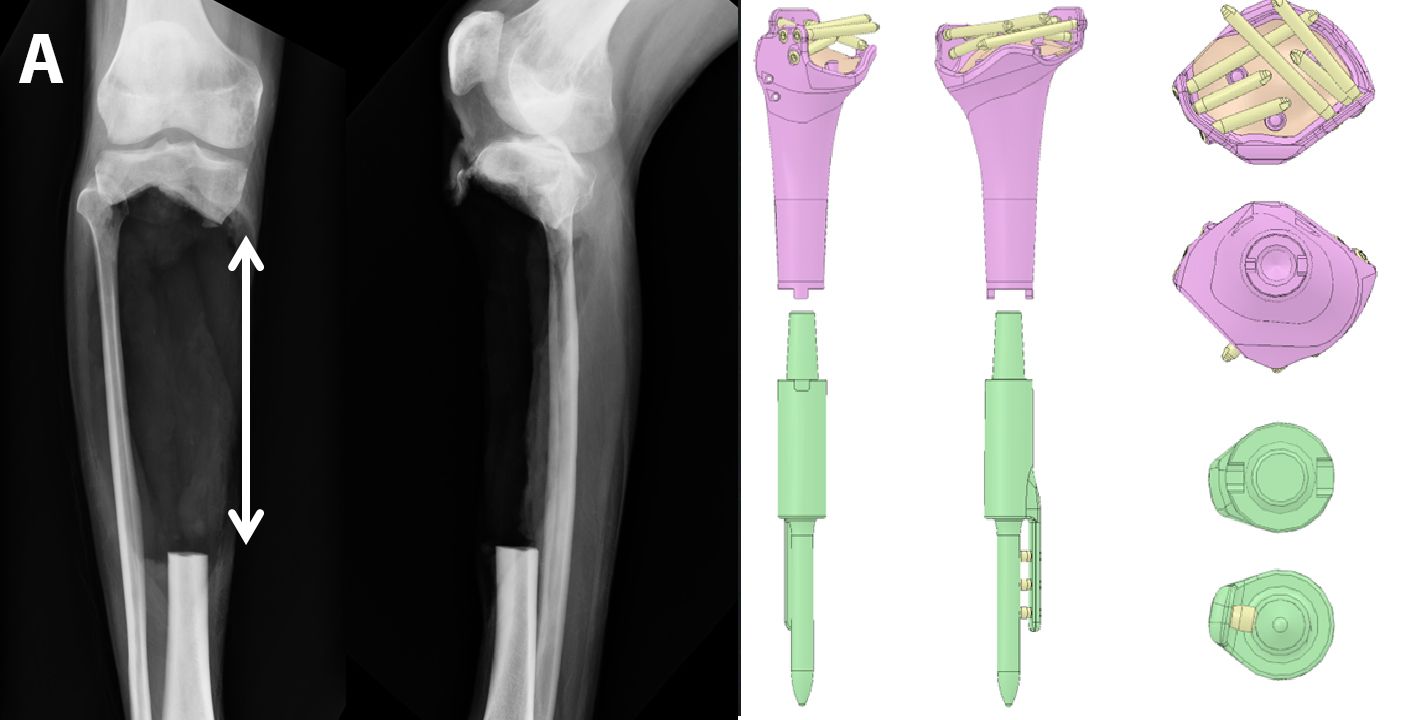

A coating for tibial nails, composed of a poly-l-lactic acid (PLLA) matrix, loaded with gentamicin, was first introduced into clinical use in Europe approximately fifteen years ago. The coating provides 80% release of the antibiotic within the first 48 hours [37]. In the first published clinical report, Fuchs et al [38] observed no deep infections at six months’ follow-up in 21 patients treated with a UTN PROtect Tibial Nail (DePuy Synthes, Bettlach, Switzerland) for closed or open tibial fractures, as well as for revisions. Metsemakers et al [39] reported a retrospective analysis, including nine patients with a Gustilo and Anderson grade II or grade III open tibial fracture, four infected nonunions, two acute tibial shaft fractures pretreated with external fixation, and one aseptic nonunion with a soft tissue defect. At 18 months’ follow-up, no implant-associated deep infection was reported. Finally, in the most recent and largest study, data from four centres, analyzed the outcome of 99 patients with fresh open or closed tibial fractures or undergoing nonunion revision surgery [40]. At 18 months’ follow-up, deep surgical site infection or osteomyelitis was noted in 4/55 patients (7.2%) after fresh fracture and in 2/26 patients (7.7%) after revision surgery. The heterogeneous material and the lack of a comparator makes the interpretation of these results particularly difficult.

Apart from the absence of comparative trials, a limit of this technology is the fact that it is only available for the tibia and for one specific nail design. Furthermore, screws and fixation holes are not protected by the coating, while gentamicin resistance, ranging from 2% to 50% in Europe [41], may reduce the efficacy of the coating in some cases.